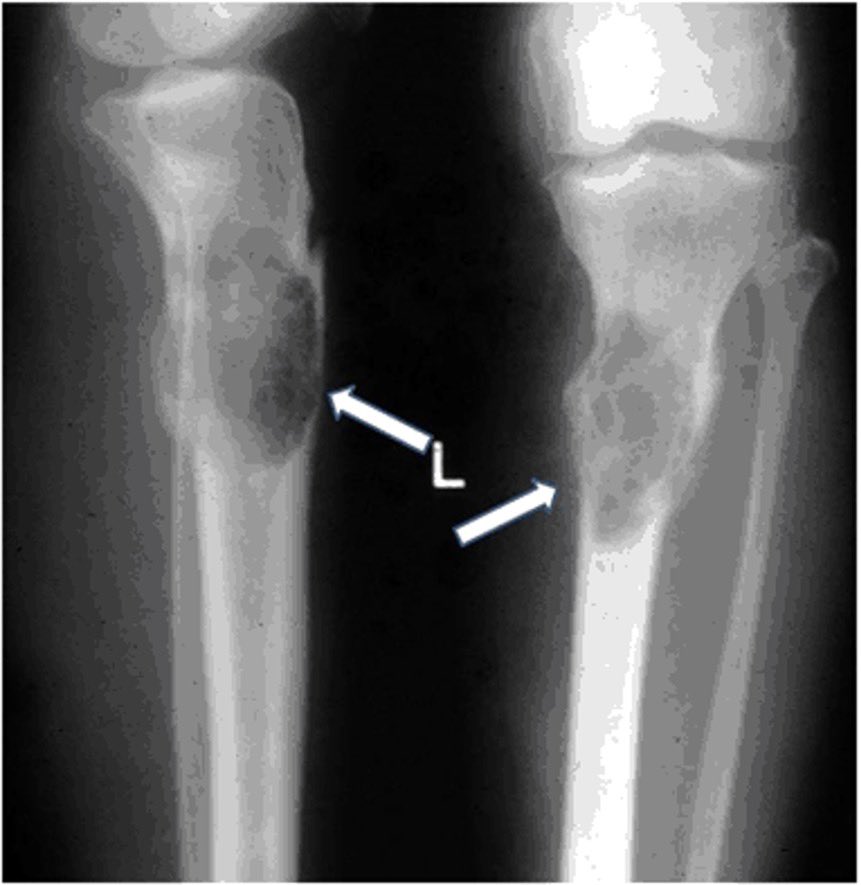

3- Renal U/S

If we saw Cysts (PCKD)

If we saw kidney small (atrophic)